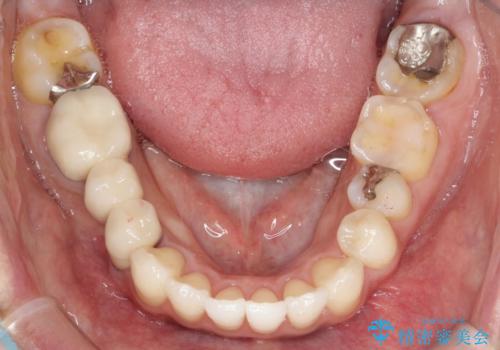

【インビザライン】矮小歯を有する方の矯正治療

- 前歯の凸凹を主訴に来院されました。

元々、歯が小さかったため矯正終了後にセラミックにて修復治療を行う治療計画をたてインビザラインにて治療を行いました。

今回はスペースを作るために歯列の拡大をメインでおこなっています。